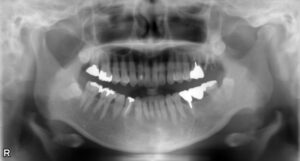

• 上顎大臼歯2本欠損症例

BEFORE AFTER 50歳女性/上2本欠損/インプラント埋込手術 【治療内容】 左上第一大臼歯、第二大臼歯は他院で…